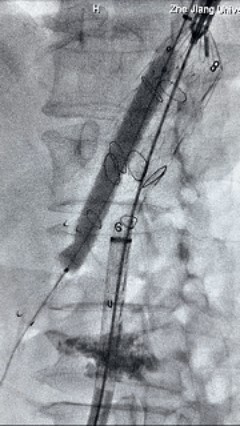

3. 经右股动脉导入超硬导丝,然后导入先健G-Branch 胸腹主动脉主体覆膜支架TAAA3418120e7i1010 一枚,释放主体支架至内分支打开,然后经左侧肱动脉入路,抓捕预置导丝成功后,将长鞘进入内分支出口处。

6. 解除束径,打开近端后释放,经肱动脉长鞘超选支架外分支,并进一步超选右侧肾动脉,交换加硬导丝,送入覆膜支架6*50mm和7*60mm各一枚,并予以球囊后扩张,手推造影显影良好。

8. 从右侧股动脉入路送入腹主支架AB-24-12-110-S,近端重叠胸腹主动脉支架远端,调整好支架位置后释放。

9. 经左股动脉送入导丝导管,超选进腹主动脉支架短腿内,后沿导丝送入髂支,同理,右侧沿导丝送入髂支并释放,使用先健顺应性球囊后扩各支架连接处及支架近远端,最后通过预留导管向瘤腔注入人纤维蛋白粘合剂数支,造影显示分支通畅。